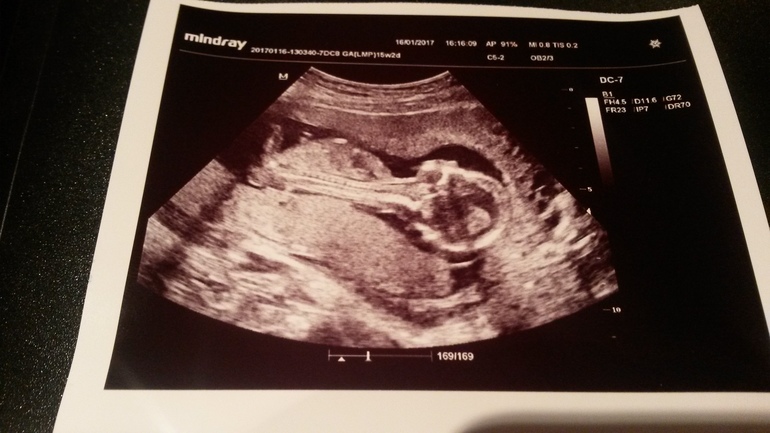

Вот и сходила я на узи

Пол малышаИ у нас будет...

ДОЧКА!ДОЧЕНЬКА!!!ДОЧУЛЯ!!!

Все узи ноги поджимала как только тётя врач датчиком пыталась посмотреть кто там)Только один раз показала,когда меня уложили на левый бок)

Плацента оказалась низко...На первом скрининге была высоко...

И переползли мы на заднюю стенку,а были по передней)